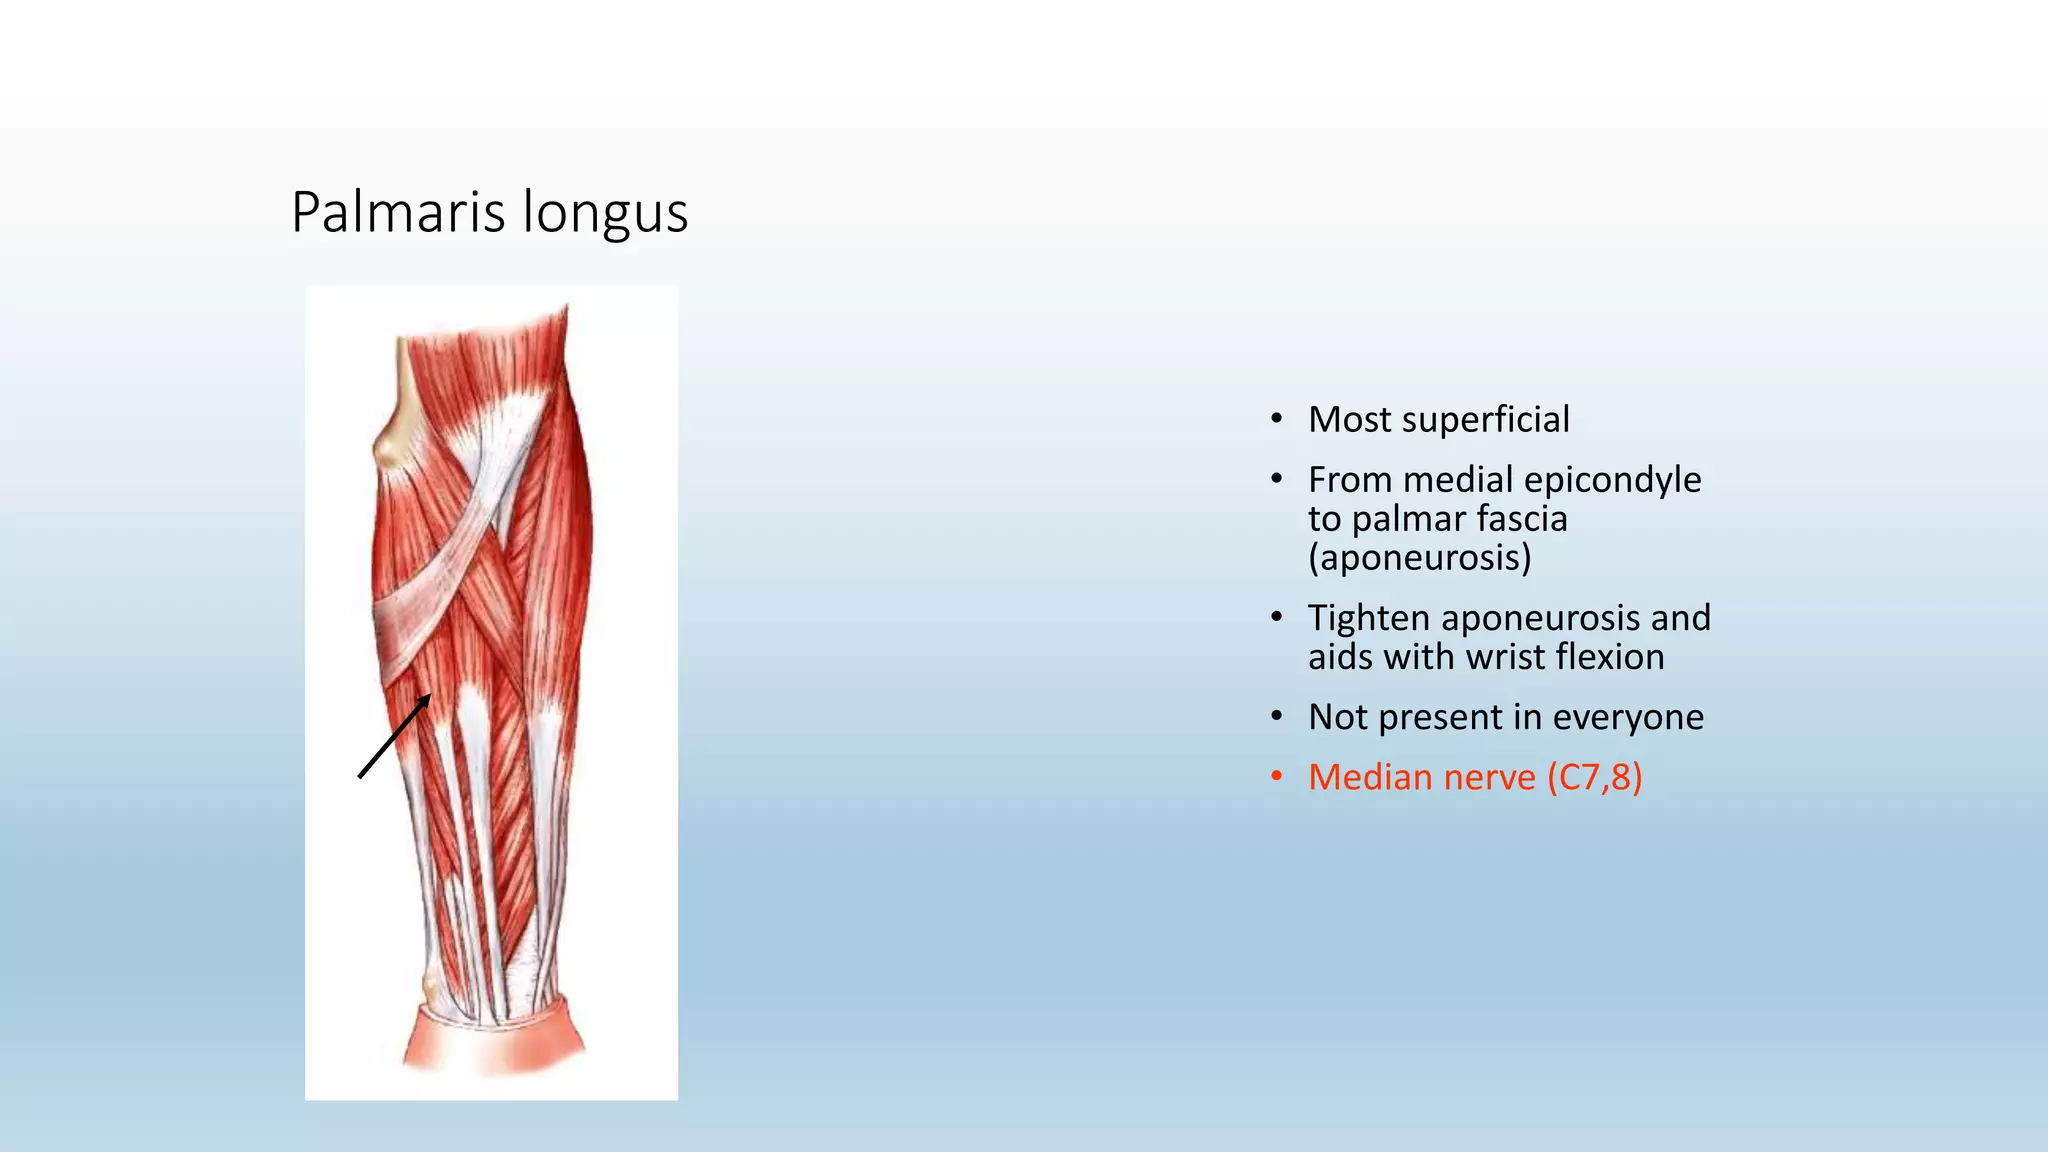

The document summarizes an anatomy revision session on the upper limb. It discusses various muscles of the upper limb including their origins, insertions, innervations and functions. Key muscles covered include the pectoralis major and minor, serratus anterior, deltoid, biceps brachii, brachialis, coracobrachialis, and triceps. It also discusses the rotator cuff muscles and muscles of the forearm including flexor carpi ulnaris and radialis. The session aims to help students identify upper limb muscles and understand their relations to nerves.